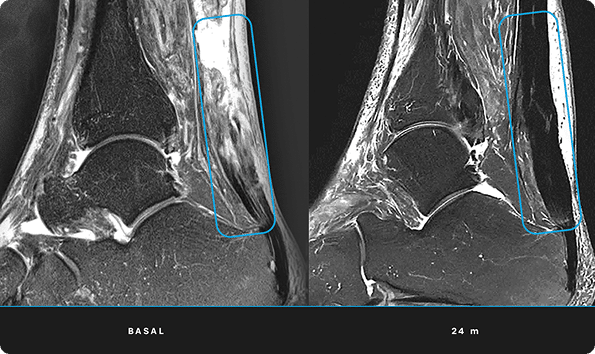

En ITRT hemos demostrado la viabilidad y seguridad de nuestras terapias mediante ensayos clínicos regulados y autorizados por la AEMPS (Agencia Española de Medicamentos y Productos Sanitarios). Una vez superado el ensayo clínico, la AEMPS autoriza el uso del medicamento en pacientes concretos, lo que permite ofrecer tratamientos personalizados con eficacia clínica y capacidad regenerativa demostrada.